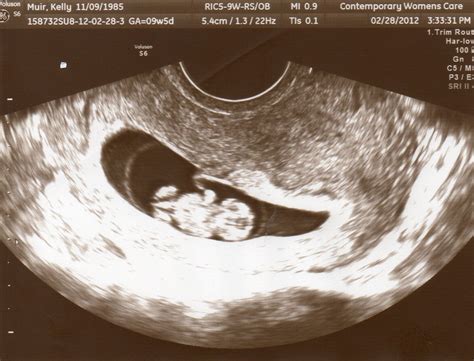

An 8 week sonogram is an ultrasound examination performed around the eighth week of pregnancy. This non-invasive procedure uses high-frequency sound waves to create images of the fetus and the uterus. The primary goal of an 8 week sonogram is to confirm the pregnancy, determine the gestational age, and assess the fetus’s development.

• Determining Gestational Age: Measuring the crown-rump length (CRL) of the fetus helps determine the exact gestational age, which is essential for monitoring the pregnancy’s progress.

• Preparation: The procedure is usually performed transabdominally, meaning the ultrasound probe is moved over the abdomen. In some cases, a transvaginal ultrasound may be used for a clearer view, especially if the uterus is tilted or the pregnancy is very early.

• Procedure: The expectant mother will lie on an examination table with her abdomen exposed. A gel is applied to the abdomen to enhance the transmission of sound waves. The ultrasound technician will then move the probe over the abdomen to capture images of the uterus and fetus.

The results of an 8 week sonogram are interpreted by a trained ultrasound technician and reviewed by an obstetrician. Key findings include:

• Gestational Age: The CRL measurement helps determine the exact gestational age, which is crucial for monitoring the pregnancy’s progress.

• Fetal Heartbeat: The presence of a heartbeat is a positive sign of a viable pregnancy.